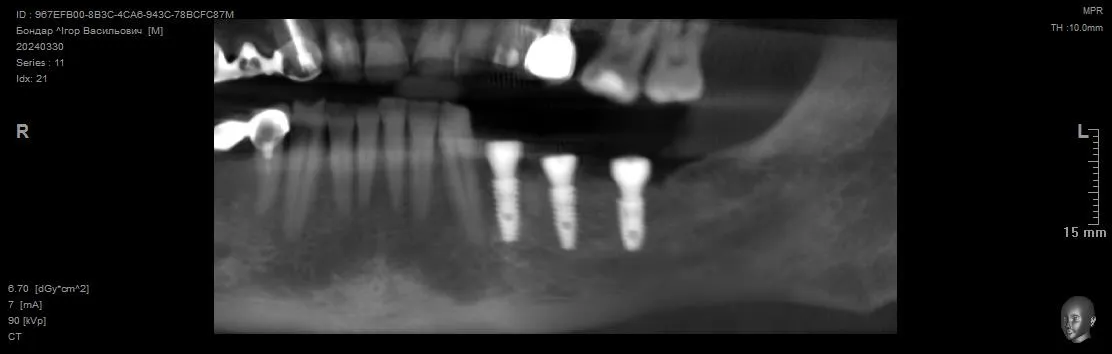

Видалення зуба 3.4 + Імплантація 3.4 3.5 3.7. Формувачі ясен. Система Neobiotech